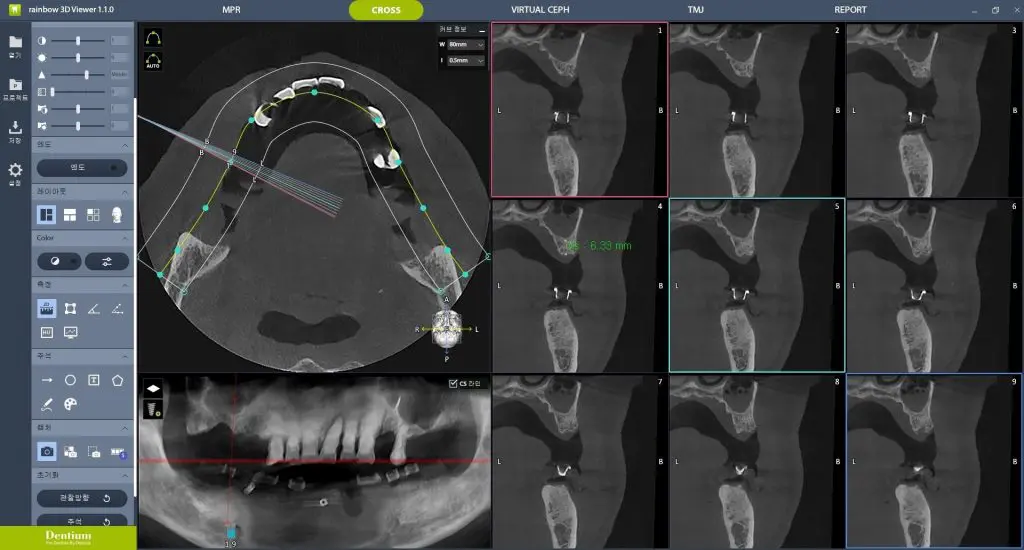

디지털 풀아치 임플란트는 한 턱에 4~6개의 임플란트로 전체 치아 기능을 회복하는 치료입니다. 먼저 3D CT, 파노라마, 디지털 구강 스캐너를 통해 잇몸뼈의 두께·밀도·신경 위치를 3차원으로 분석합니다. 이 단계에서 임플란트가 가능한 뼈 영역과 피해야 할 위험 구간을 명확히 구분합니다.

수집된 데이터를 기반으로 컴퓨터 상에서 가상 수술을 먼저 진행합니다. 임플란트의 개수, 위치, 각도, 깊이를 모두 수치로 계산하며, 뼈이식이 필요 없는 최적의 식립 지점을 우선적으로 설계합니다. 이 과정 덕분에 수술은 감각이 아닌 계획 기반으로 진행됩니다.